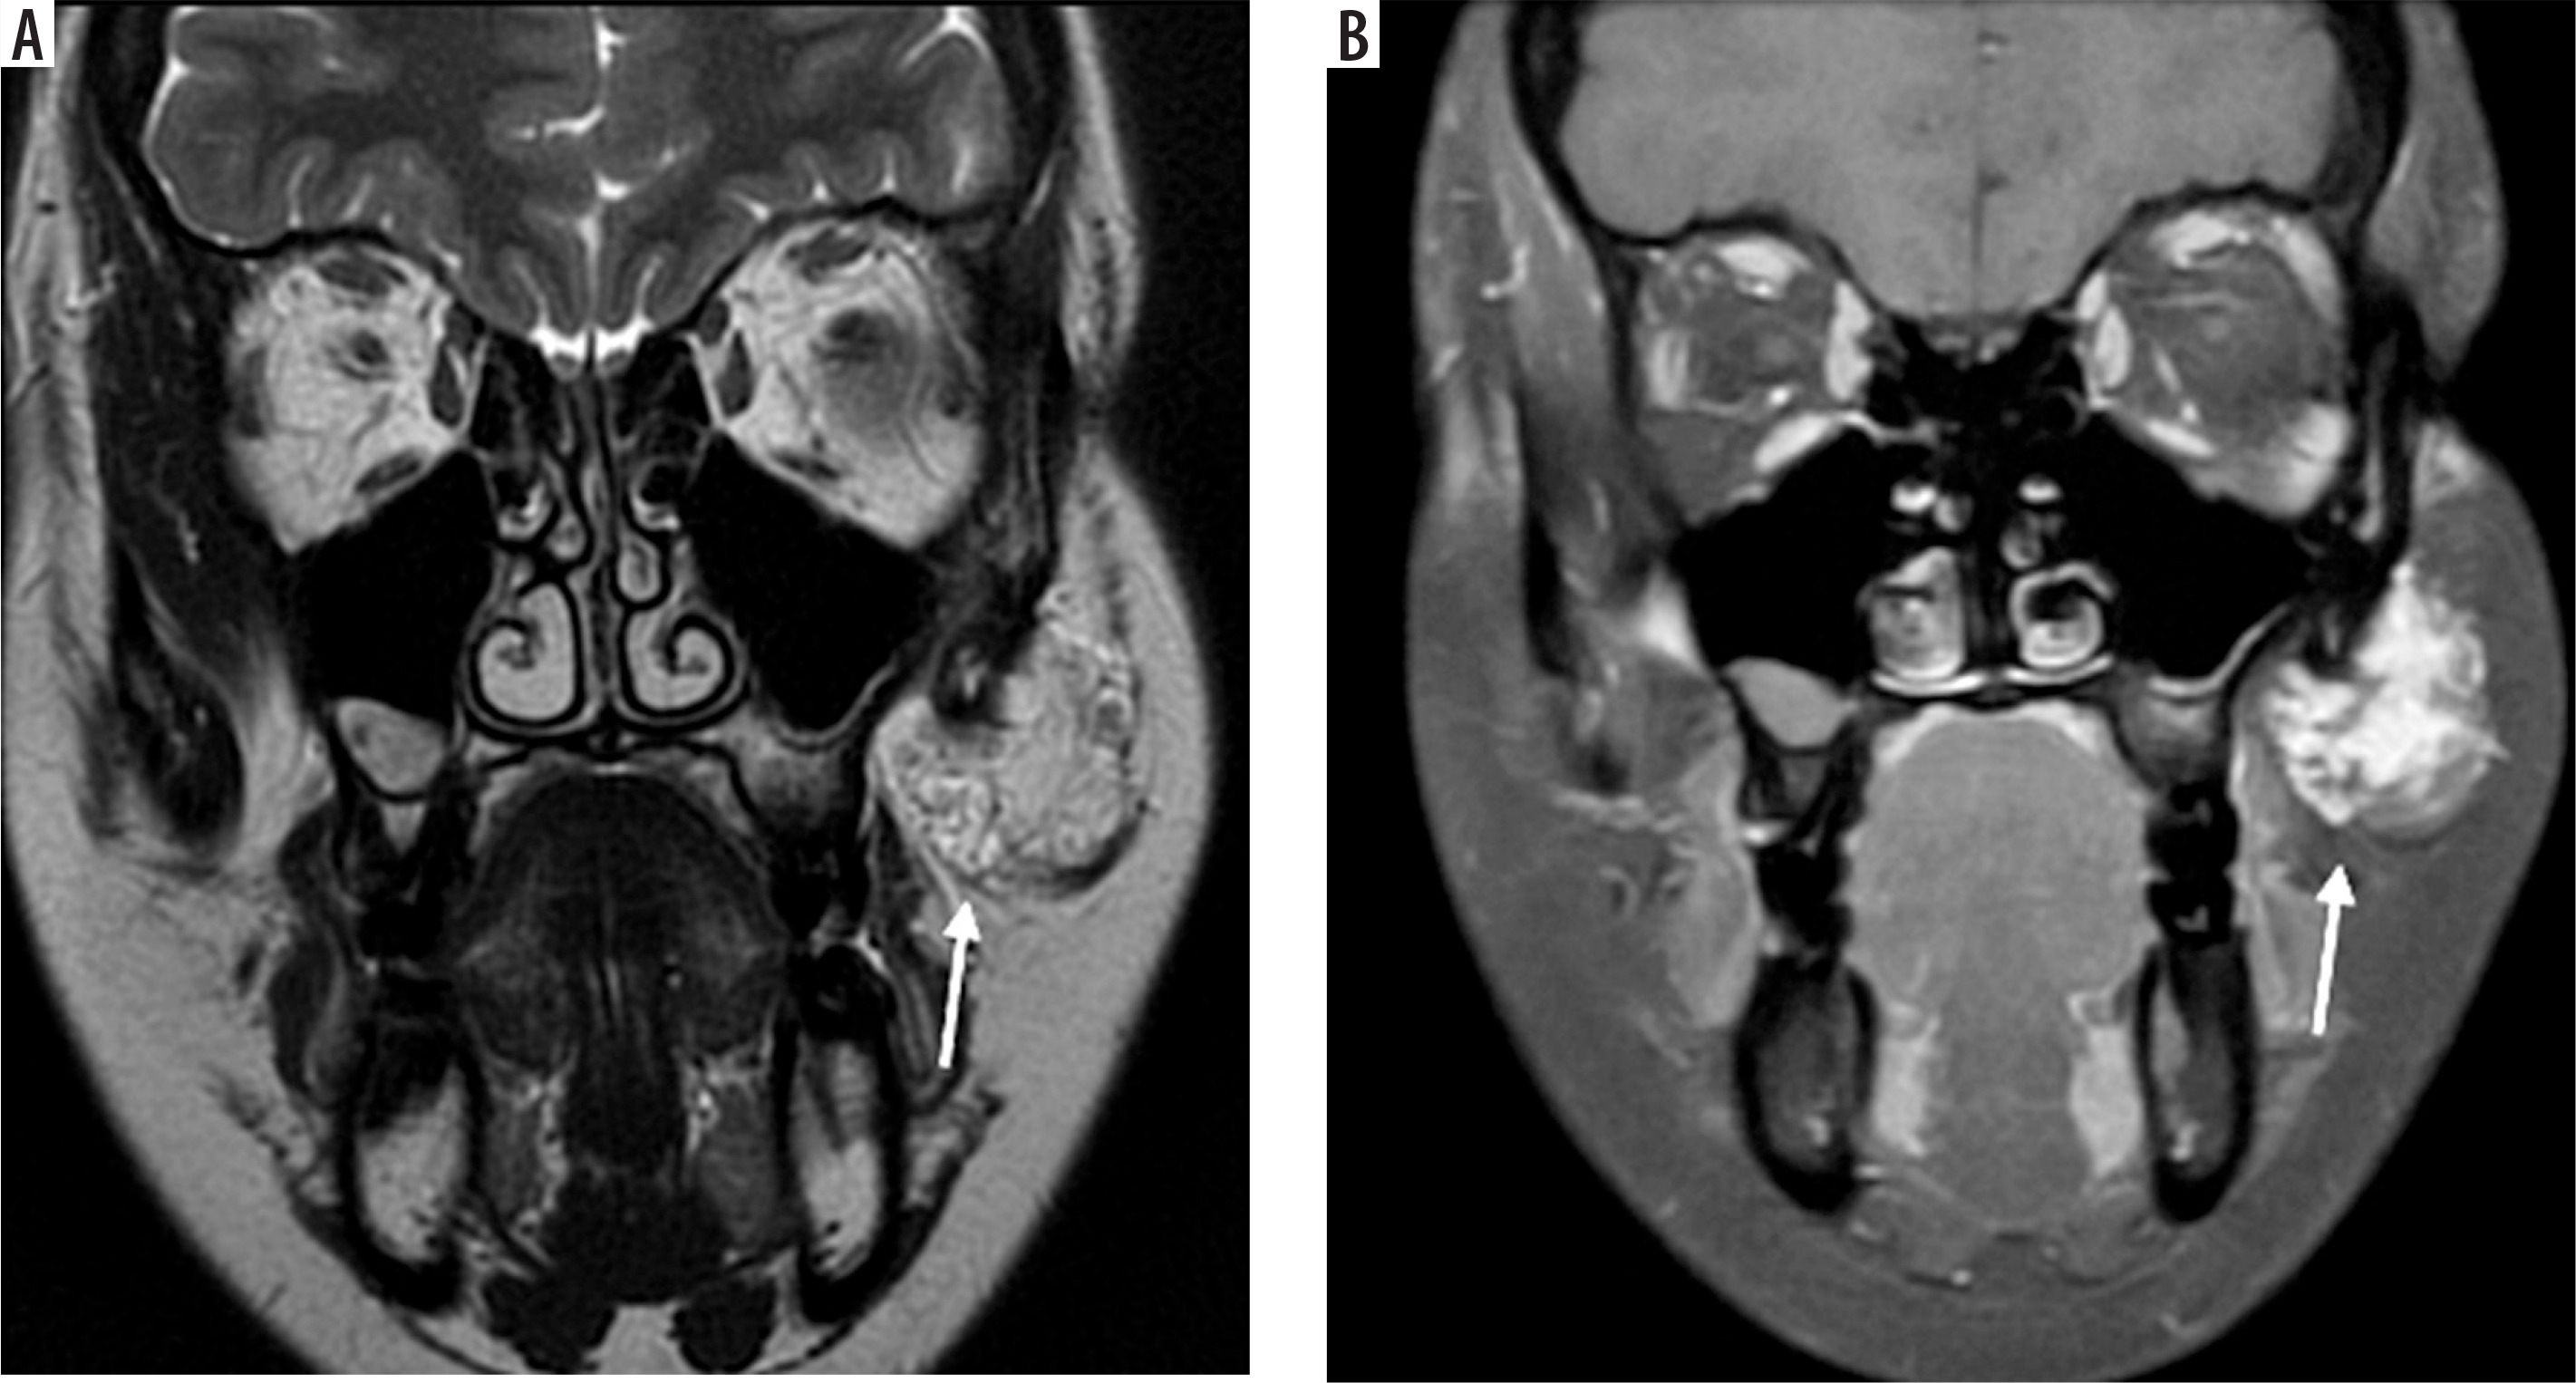

Case 5: Normal TMJ anatomy and disk displacement without reduction

On the MRI shown in Figure 8A, note that the cortex of the condyle is hypointense because there is no fluid or fat in the cortex. The same applied to the articular eminence and glenoid fossa, which show a hypointense outline. Also, note that within the articular eminence and condyle there are hyperintense signals because of fatty bone marrow contained within. The articular disk between the articular eminence and condyle is hypointense and shows a normal biconcave shape, and the posterior band of the disk end at the 12 o’clock position of the head of the condyle in close position (Figure 8A). In an open position, the articular disk is between the articular eminence and maintains a normal biconcave shape. Note the posterior flaring of the disk, and at least 50% of the disk is behind the contact point between the condylar head and articular eminence (Figures 8A-B). Assessing the disk and surrounding structures in TMJ dysfunction is the most important part for diagnosing internal derangement of TMJ in MRI, and the sagittal view is the most useful view for that [22]. The ability of MRI to produce precise images of the joint and surrounding structures without the use of ionising radiation, which is a possible concern associated with conventional imaging techniques such as X-rays and CT scans, is one of the main reasons for using MRI for the TMJ [22,23]. The MRI shown in Figure 8C in the open position shows the disk located anteriorly, which indicates a pathological condition of anterior disk displacement without reduction (Figure 8C).

Figure 8

Sagittal view of T1-weighted MRI images. A) Normal TMJ in closed position, B) normal TMJ in opened position C) anterior disk displacement without reduction. 1, articular eminence, 2, intermediate band of articular disk, 3, mandibular condyle, 4, retrodiscal tissue, 5 and 6 superior and inferior bellies of the lateral pterygoid muscle. Identifying internal derangements of the TMJ is crucial for accurate diagnosis and for planning both conservative and surgical interventions in TMJ disorders. [Figure 7A and 7B, Courtesy: Radiopaedia. DOI: https://doi.org/10.53347/rID-2748, rID: 2748; Figure 7C, Courtesy: Radiopaedia. DOI: https://doi.org/10.53347/rID-66812, rID: 66812]